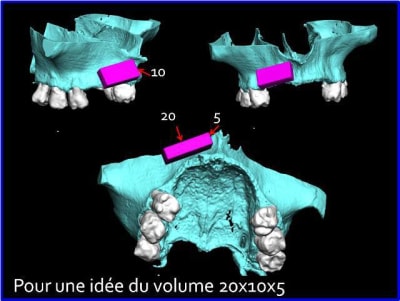

L’idée de base est d’obtenir un greffon adapté à la zone à greffer, et de donner plus de chance à la nature de faire son travail de reconstruction.

Dans un premier temps, les greffons sont préparés manuellement par votre serviteur, mais ensuite la machine outil prendra le relais, dés que seront résolus les petits problèmes d’environnement.

Une fois les greffons préparés, ils sont traités par un procédé spécifique à Biobank (CO2 supercritique) puis stérilisation (rayons gamma), et vous le verrez la pose devrait être extrêmement simplifiée.

l'étude en partant des blocs standards

c'est un bonne idée, obtenir des blocs usinés sur mesure (je comprends pourquoi Mr Bardonney m'a demandé par mail si je trouvais interessant de ne pas avoir à adapter moi-même la forme du greffon :)

Il faut que Biobank dispose d'une petite machine d'usinage genre cerec qui pourrais usiner les intrados de greffon d'après les fichiers élaborés par posit?

La première diapo est un essai pour justifier le concept (os non destiné à une utilisation greffe)

la deuxième est "tapée" dans une tête de femur de mauvais qualité (rejetée)

la troisième et suivante ce sont "les greffons" définitifs.

Pour la mise en forme de la pièce 1 (appui 12) avec la mise en place, le choix de la tête de fémur, et les discussions pour expliquer la mise en forme, il a fallu 1 h environ, qui pourrait etre réduite à une trentaine de minutes, dans un cas comme celui ci, ce qui est déjà énorme pour l'os d'un patient (mise à nu ect...), sans parler des différents stress.